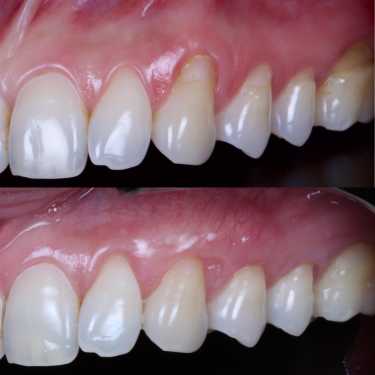

RECOBRIMENTO RADICULAR

É uma cirurgia realizada na gengiva para recobrir raízes expostas de dentes com recessão radicular. Nesses dentes a gengiva retrai e eles ficam parecendo mais compridos. O procedimento consiste no reposicionamento da gengiva em seu local correto, melhorando a aparência do sorriso e eliminando a sensibilidade que normalmente está presente.